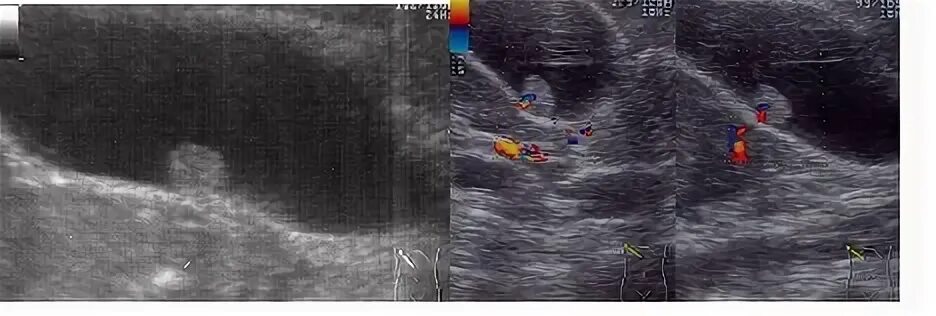

Полип желчного пузыря операции